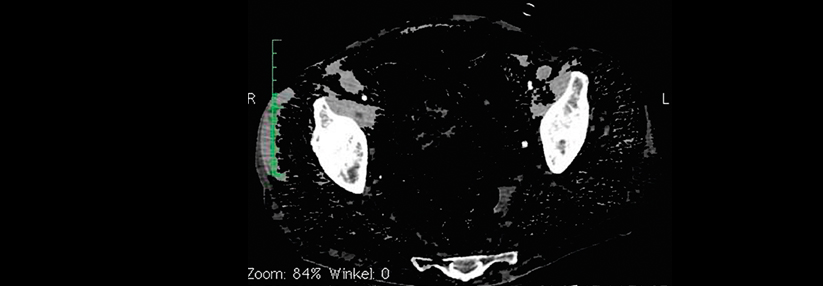

Außerdem hatten die Teilnehmer mit Hypertriglyzeridämie signifikant häufiger intrakranielle Gefäßstenosen, schreiben Takao Hoshino von der Abteilung für Neurologie, Women’s Medical University Hospital in Tokio, und Kollegen. Das triglyzeridbedingte erhöhte Risiko für Gefäßereignisse betraf unter den Patienten mit atherothrombotischem Apoplex sowohl diejenigen mit signifikanten intrakraniellen Stenosen als auch die mit einer Stenose der A. carotis. Mit rezidivierenden Episoden kardioembolischer Schlaganfälle war die Hypertriglyzeridämie indes nicht assoziiert.